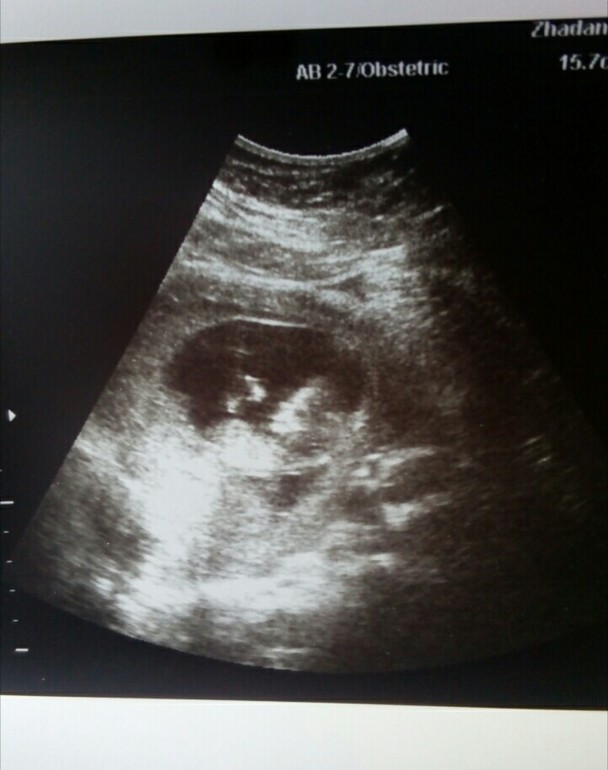

Всем приветик, сегодня 12 ,1 недели и мы пошли на скрининг, переживала ооооочень,но все прекрасно, спасибо Господи,за нашего малыша, КТР 52 мм, носовая кость есть , твп 1,2,развивается по акушерским неделям ,12,2,чсс 160,пол не сказали,но сказала что больше похоже на девочку, я несколько раз спросила все ли в норме, она улыбаясь ответила да)))

Ну и фоточка в придачу

Улыбаемся и машем, малыш был очень активный)))но это потому что мамка переживала